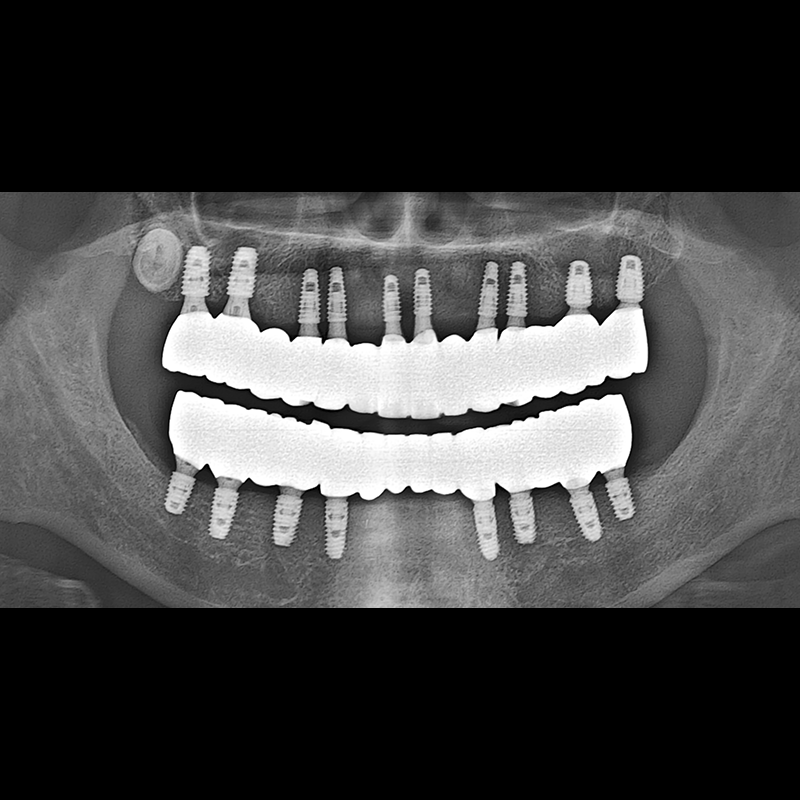

IMPLANT

BEFORE AFTER

임플란트 전후사진 2025.05.30

결손된 치아 부분과 살리기 힘든 치아 위치에 임플란트를 식립하였습니다.